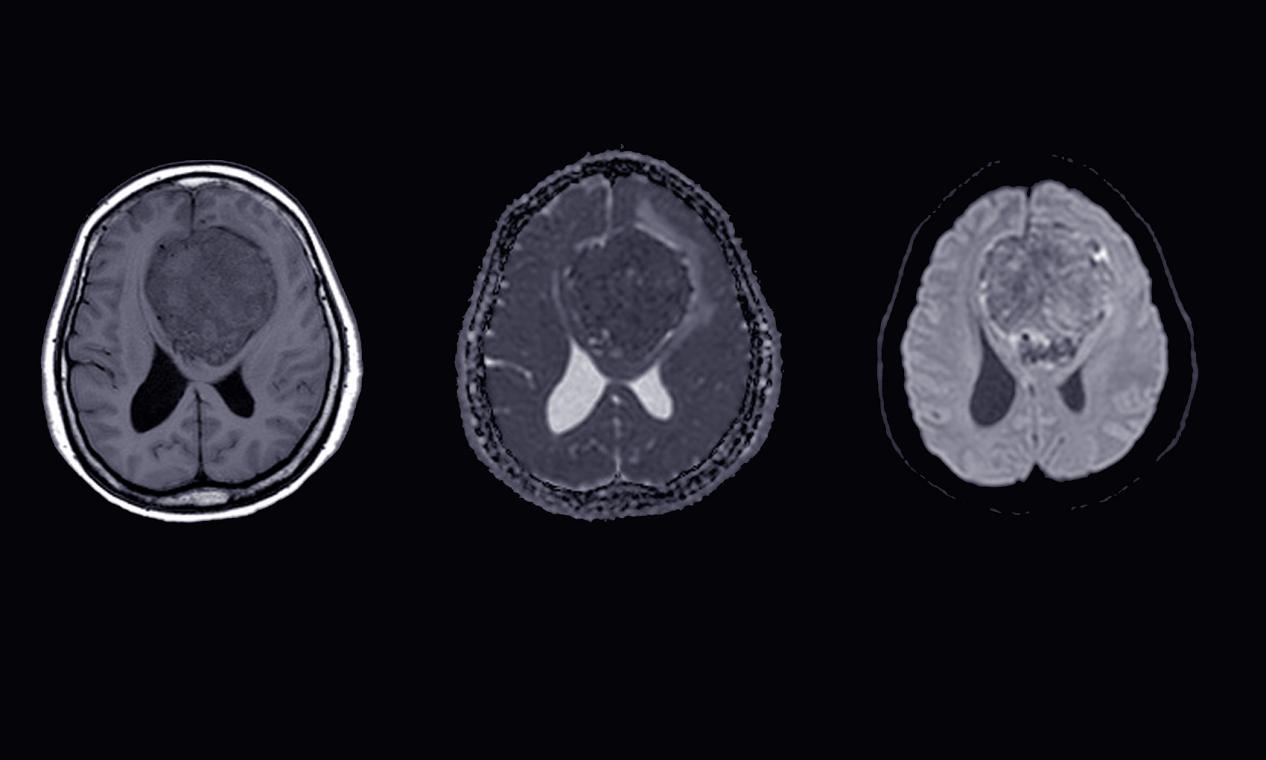

脑膜瘤的早期症状,昆明脑膜瘤医院推荐-昆明医科肿瘤医院脑膜瘤(Meningiomas)是起源于脑膜及脑膜间隙的衍生物,发病率占颅内肿瘤的19.2%,居第2位,女性:男性为2:1,发病高峰年龄在45岁,儿童少见。许多无症状脑膜瘤多为偶然发现。脑膜瘤是一种起源于脑...

昆明脑膜瘤放射治疗方式,昆明脑膜瘤医院哪家好-昆明医科肿瘤医院脑膜瘤(Meningiomas)是起源于脑膜及脑膜间隙的衍生物,发病率占颅内肿瘤的19.2%,居第2位,女性:男性为2:1,发病高峰年龄在45岁,儿童少见。许多无症状脑膜瘤多为偶然发现。脑膜瘤是指发...